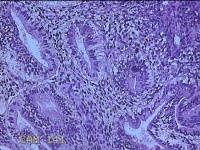

子宫腔赘生物

性别

女

年龄

33岁

临床诊断

子宫内膜息肉?子宫异常出血

一般病史

阴道流血12天。

标本名称

大体所见

灰白粉红色不规则肿物1.5x1.3x0.2cm一堆,表面糜烂。

图3